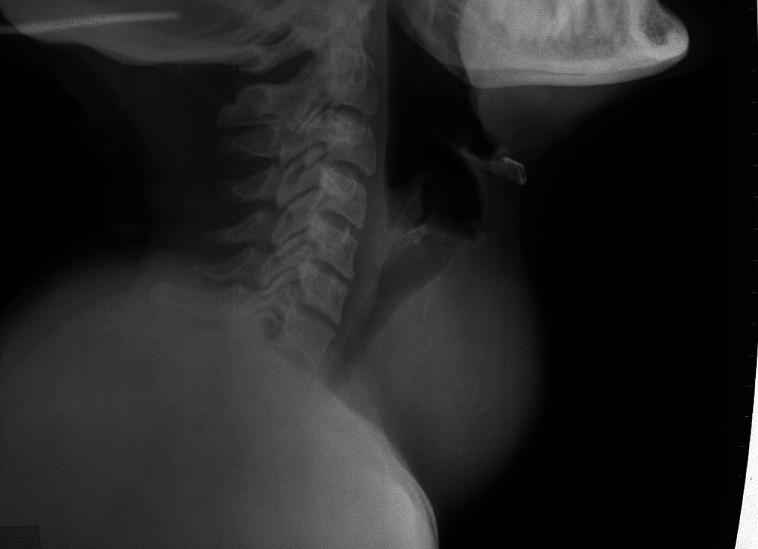

Thyroidectomy is the most common endocrine surgical procedure being carried out throughout the world. Besides, many patients who have deranged thyroid physiology, namely hyperthyroidism and hypothyroidism, have to undergo various elective and emergency surgical procedures at some stage of their life. The attending anesthesiologist has to face numerous daunting tasks while administering anesthesia to such patients. The challenging scenarios can be encountered at any stage, be it preoperative, intra-op or postoperative period. Preoperatively, deranged thyroid physiology warrants optimal preparation, while anticipated difficult airway due to enlarged thyroid gland further adds to the anesthetic challenges. Cardiac complications are equally challenging as also the presence of various co-morbidities which make the task of anesthesiologist extremely difficult. Thyroid storm can occur during intra-op and post-op period in inadequately prepared surgical patients. Postoperatively, numerous complications can develop that include hemorrhage, laryngeal edema, nerve palsies, tracheomalacia, hypocalcemic tetany, pneumothorax, etc., The present review aims at an in-depth analysis of potential risk factors and challenges during administration of anesthesia and possible complications in patients with thyroid disease.

甲状腺切除术是全球最常见的内分泌外科手术。此外,许多甲状腺生理功能紊乱的患者,即甲亢和甲减患者,在其人生的某个阶段不得不接受各种择期和急诊外科手术。主治麻醉医生在为这类患者实施麻醉时必须面对众多艰巨任务。在术前、术中或术后的任何阶段都可能遇到具有挑战性的情况。术前,甲状腺生理功能紊乱需要进行最佳准备,而由于甲状腺肿大导致的预期困难气道进一步增加了麻醉挑战。心脏并发症同样具有挑战性,各种合并症的存在也使麻醉医生的任务极其困难。准备不充分的手术患者在术中及术后可能发生甲状腺危象。术后,可能会出现多种并发症,包括出血、喉水肿、神经麻痹、气管软化、低钙性手足搐搦、气胸等。本综述旨在深入分析甲状腺疾病患者麻醉管理过程中的潜在危险因素和挑战以及可能出现的并发症。